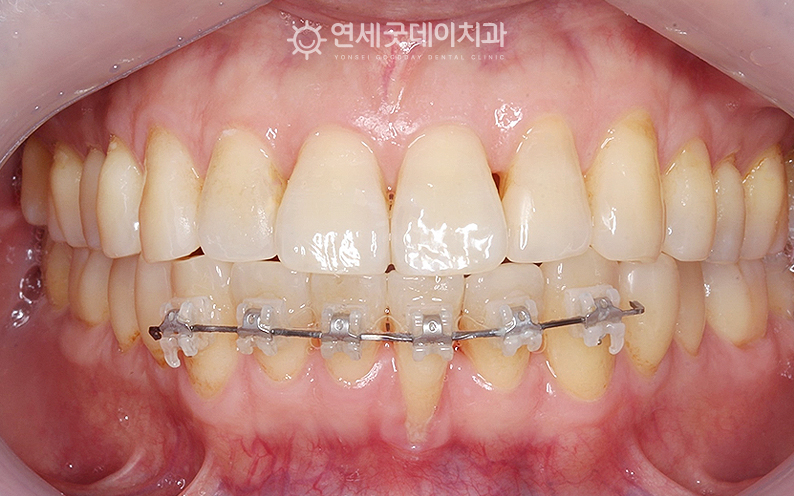

▲ 아랫니부분교정 진행 중 (촬영시기 : 2025년 5월)

약 5개월 간의 아랫니부분교정만으로도

‘치주교정’은 잇몸뼈 밖으로 돌출된 치아를